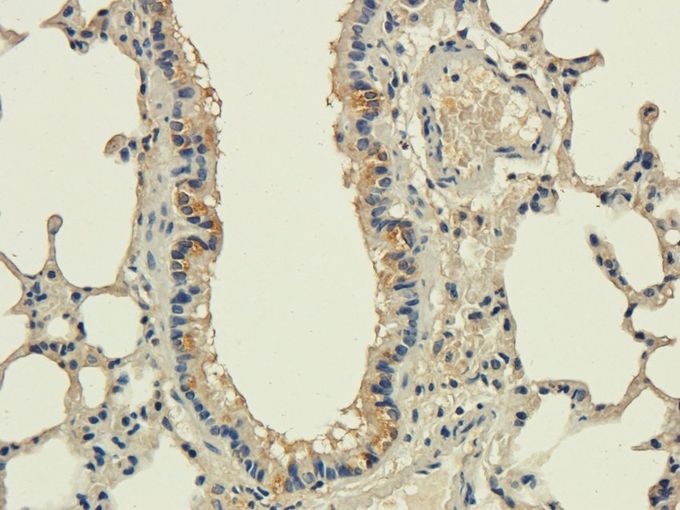

IHC-P analysis of rat ovary tissue using GTX37446 CD83 antibody.

Dilution : 2.5μg/ml